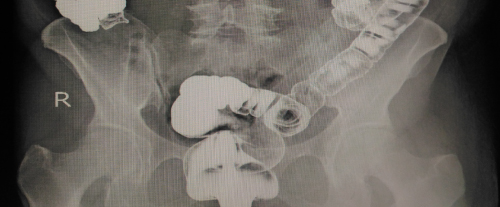

Cáncer de colon

Evaluación, diagnóstico y tratamiento quirúrgico.

Cáncer de recto

Manejo médico-quirúrgico

y especializado.